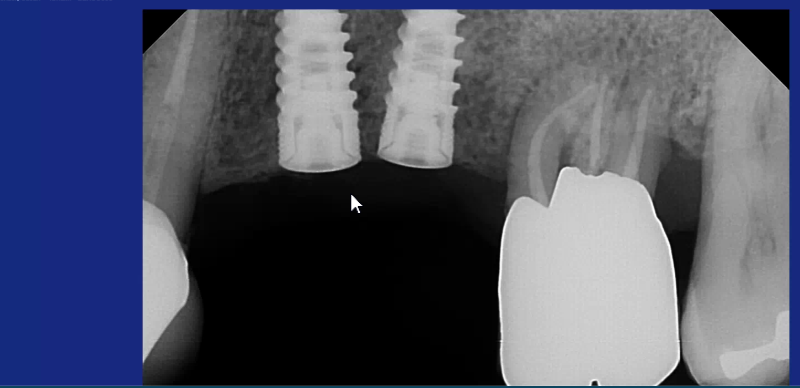

These 2 implants were placed 2 years ago and are fully integrated. There angulation and proximity are very close. I am planning the secondary surgery but anticipating difficulty. Please comment on how you would approach this restorative process.

Yes, you’re right, that might be a problem which is why I said that you might lose your retentive features of your impression copings. I would try it and see though. I don’t think that they look too bad from your radiographs and the chances are that they might diverge bucco lingually too. That will help you to get them both in place whilst maintaining as much retention as you can on the copings. Yes, you could use stock abutments but they may not be retentive enough and strip out of the impression as you remove it. Also, in most systems, there is a choice of impression coping lengths which might help. Anyway, I would give it a go and see how you get on.Barrow Marks comments: